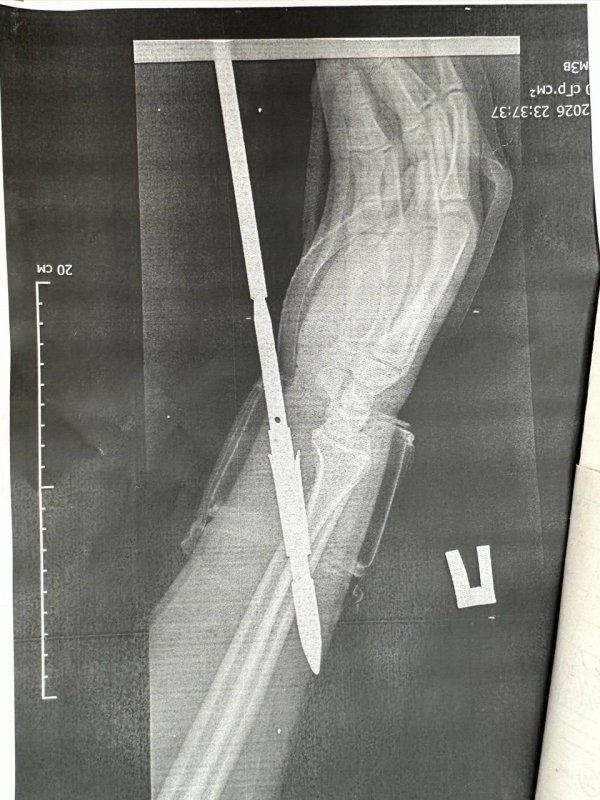

Как рассказали врачи, гарпун с двумя зубцами прошёл между костями — обошлось без перелома. Специалисты аккуратно извлекли инородное тело, обработали рану и оказали всю необходимую помощь.

Фото: ГАУЗ «ГБ» г. Орска